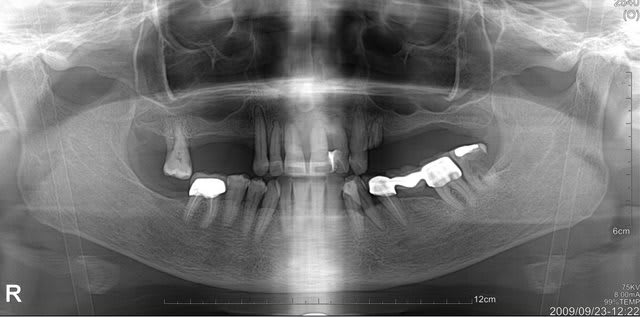

Pour ce cas, au maxillaire, la patiente a accepte un devis de 3500€ pour un complet sur barre avec 4 implants.

sur la deuxieme photo, j'ai notifie des longueurs approximatives pour les epaisseurs d'os disponibles.

Que pensez vous d'un all on 6 avec les 6 anterieurs ?

Ps: la patiente n'a pas forcement les moyens de faire un bridge sur 8 implants...

patiente motivée et sympa, sourire pas du tout gingival, de l'os assez bien exploitable (un peu moins du cote de 25-26, mais je vais me débrouiller soit avec implants courts 6 ou 8mm, soit avec une Summers et poser des 10mm)

Niveau nombre d'implants , je vais plutôt tabler soit sur 8 ou 9 implants et remplacer de 16 à 26.